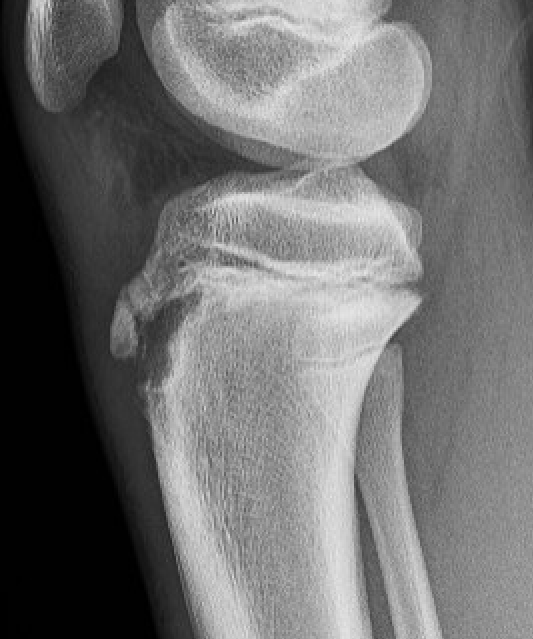

Type IB

Type IIB

Type III

Comminuted Type III